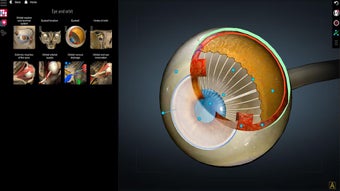

Anatomy Learning - 3D Atlas è un'app gratuita per Android che appartiene alla categoria Medicina ed è stata sviluppata da AnatomyLearning. È consigliata per principianti, studenti di medicina, apprendisti visivi, professionisti medici, medici.

Questa app è meglio conosciuta per le seguenti caratteristiche e qualità: strumento di studio, apprendimento dell'anatomia, strumento di apprendimento e riferimento di base.